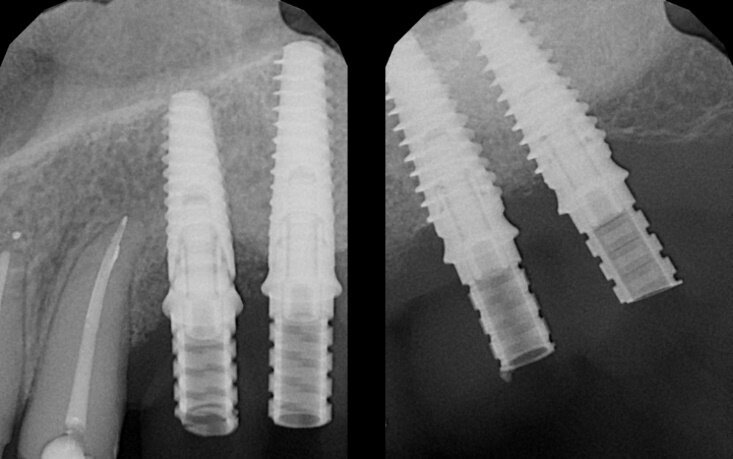

Fig. 6 - Fase di inserimento implantare. Al sollevamento del lembo si osserva la rigenerazione avvenuta in posizione 2.4 e 2.5 e si procede all’inserimento di quattro impianti osteoingrati; il prelievo del campione bioptico avviene in corrispondenza all’elemento 2.7. A destra, radiografia endorale degli impianti appena inseriti.

La CBCT post-chirurgica evidenziava in posizione 2.4 un aumento dello spessore osseo da 8,5 a 9,2 mm e della distanza cresta/pavimento naso da 4,4 a 15,2 mm (+8,8 mm). In posizione 2.6 lo spessore osseo era aumentato da meno di 1 mm a 12,6 mm, con 16 mm di profondità intra-sinus (+15 mm) (Fig. 5). La rimozione delle suture è avvenuta dopo 10 giorni. A sei mesi, l’esame CBCT evidenziava in posizione 2.4 una contrazione fisiologica da 9,2 a 7,2 mm in spessore e da 15,2 a 14,2 mm in altezza, mentre il volume rigenerato nel seno appariva invariato (14,4 e 15,9 mm). Dopo profilassi antibiotica e anestesia con le modalità già descritte, si è sollevato un lembo a tutto spessore e sono stati posizionati quattro impianti (OXY K1, Biomec S.r.l, Colico, Lecco) nelle posizioni da 2.4 a 2.7 (2.4, 3,5 x 15 mm; 2.5, 3,5 x 13 mm; 2.6 e 2.7, 4,5 x 11,5 mm).

Tutti gli impianti sono stati inseriti con torque ≥ 30 Ncm. Gli impianti utilizzati presentano un filetto esterno a doppio principio con passo della spira di 1,8 mm e distanza tra le spire di 0,9 mm; la superficie è sottoposta a doppio attacco chimico, decontaminata e trattata con plasma Argon a freddo. Durante l’inserimento dell’impianto in posizione 2.7 è stato prelevato un campione bioptico per l’analisi istologica e istomorfometrica (Fig. 6). A tre ore dall’intervento sono stati posizionati 4 provvisori avvitati, immediatamente caricati, con pilastri a connessione conica interna. La paziente è stata riabilitata definitivamente sei mesi dopo il posizionamento implantare.